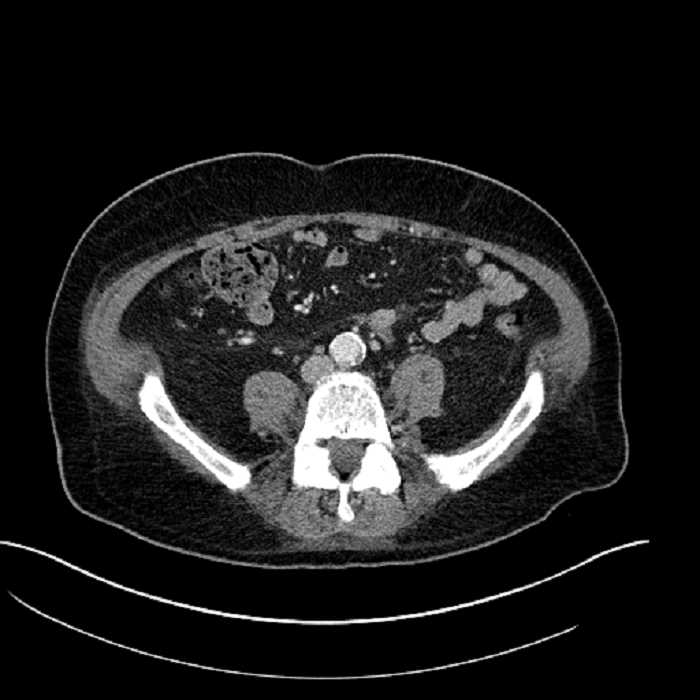

Age: 63

Sex: Male

Indication: Abdominal pain

• Mild mural thickening of a segment of the sigmoid colon with adjacent fat stranding and a 1.5 cm fluid and gas collection along the tip of an inflamed diverticulum

• Loss of the normal fat plane between this collection and adjacent loops of small bowel, which demonstrate mural thickening

Acute sigmoid diverticulitis complicated by a small contained perforation and a large abscess in the right hepatic lobe. Additional small subcapsular abscesses along the anterior margin of the left hepatic lobe.

Additionally, loss of the normal fat plane between the peridiverticular collection and adjacent thickened loops of small bowel raises the potential for an enterocolonic fistula.

Hepatic abscess showing the double target sign with low density internally surrounded by a thin inner enhancing rim (red arrow) and ill-defined outer low density rim (yellow arrow). Blue arrow indicates an internal septation. Red arrows: additional smaller subcapsular abscesses. Red arrow: focal contained perforation associated with diverticulitis.